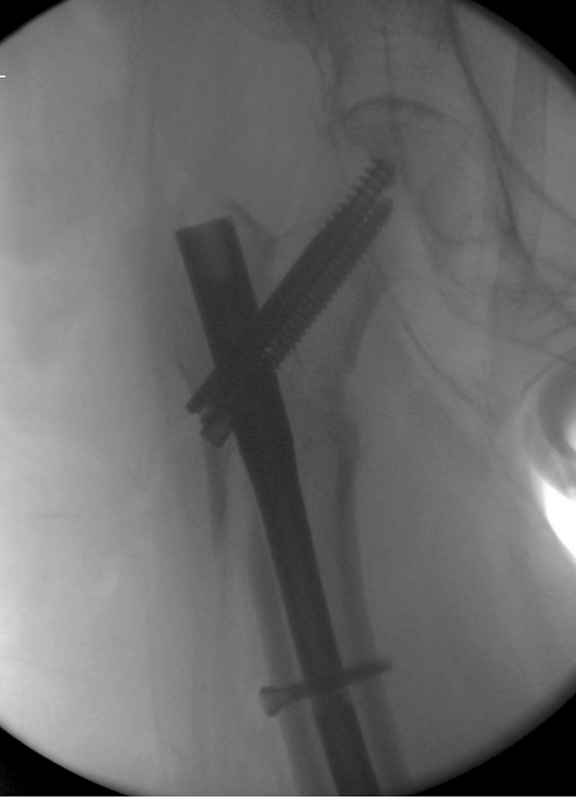

Re: Чрезвертельный перелом бедра

послал Djoldas Kuldjanov 25 Август 2009, 22:19

Здесь 83 года, травма в результате падения